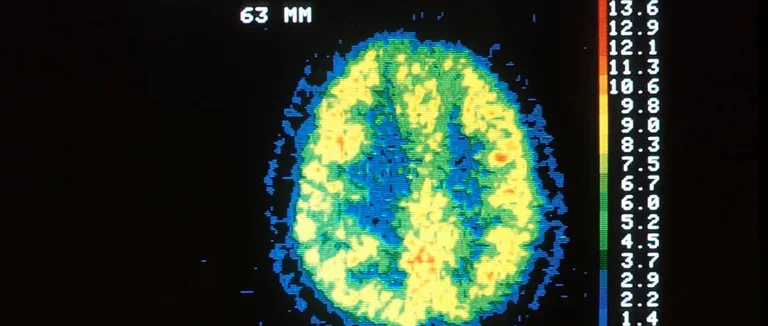

La TEP est une méthode d'imagerie qui montre comment le cerveau fonctionne. Elle aide beaucoup dans le diagnostic de la démence et de l'Alzheimer.

La TEP utilise un traceur radioactif injecté dans le corps. Ce traceur se lie aux plaques amyloïdes, comme celles de l'Alzheimer. Les positons émis par le traceur sont capturés par une caméra.

Cette technique montre les changements métaboliques dans le cerveau. Elle est non invasive et très utile pour voir l'activité cérébrale.

La TEP montre comment le cerveau fonctionne, différent de l'IRM ou du scanner CT. Ces derniers montrent plutôt la structure du cerveau. La TEP détecte les changements métaboliques avant les changements structurels.

Elle permet d'évaluer l'activité métabolique. C'est pourquoi la TEP est très utile pour diagnostiquer tôt la démence et suivre l'évolution de l'Alzheimer.

Le TEP au FDG est très utilisé pour voir le métabolisme du cerveau. Il montre comment le glucose est utilisé dans le cerveau. C'est crucial pour diagnostiquer la maladie d'Alzheimer et d'autres démences.

Le FDG est comme du glucose qui se lie aux cellules cérébrales selon leur activité. Les zones moins actives apparaissent comme des zones hypométaboliques. Cela montre des dommages ou une dégénérescence.

La TEP cérébrale aide à comprendre les changements métaboliques liés à la démence. Pour bien interpréter les résultats, il faut connaître les signes spécifiques de la maladie d'Alzheimer et d'autres formes de démence.

Modèles métaboliques caractéristiques de la maladie d'Alzheimer

Les scans TEP au FDG examinent le métabolisme du cerveau. Les personnes atteintes de la maladie d'Alzheimer ont moins de glucose dans certains endroits du cerveau. Cela inclut les lobes temporaux et pariétaux.

Ces changements peuvent se voir avant les premiers symptômes. Cela permet de commencer le traitement plus tôt.